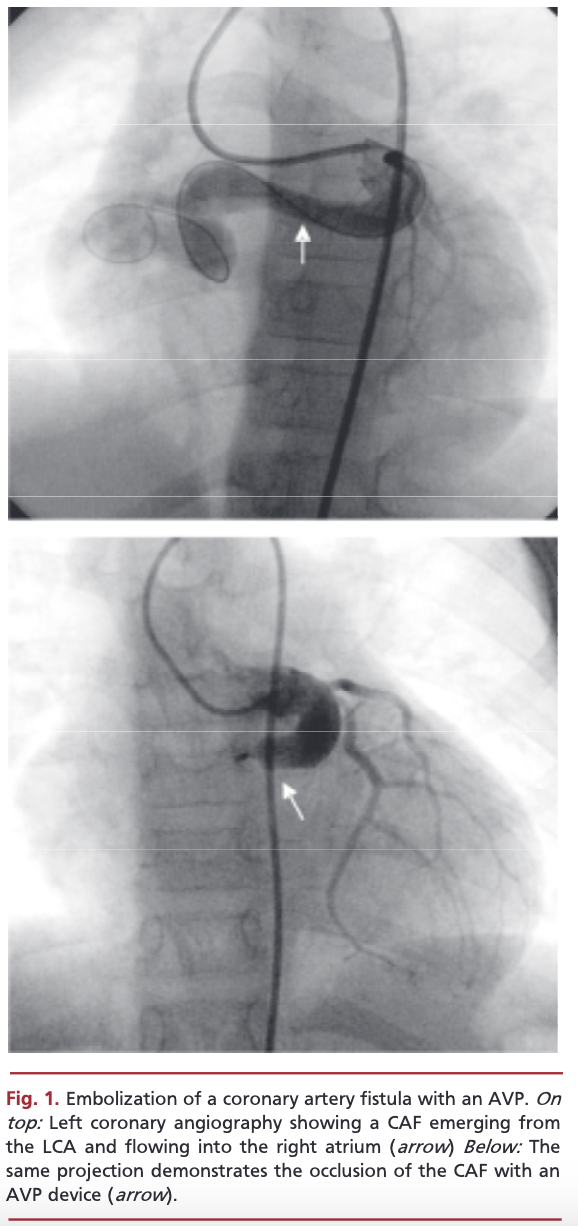

La fístula coronaria congénita es una patología poco frecuente y en general asintomática, por lo que muchas veces se diagnostica por un hallazgo incidental. Con dependencia de la repercusión hemodinámica, algunos siguen una conducta conservadora, otros indican tratamiento quirúrgico o, más recientemente, oclusión por cateterismo. Se presenta el caso de una paciente con una gran fístula coronaria-cameral, que se trató mediante embolización percutánea con dispositivo Amplatzer vascular plug. No se presentaron complicaciones durante el procedimiento ni en el seguimiento.